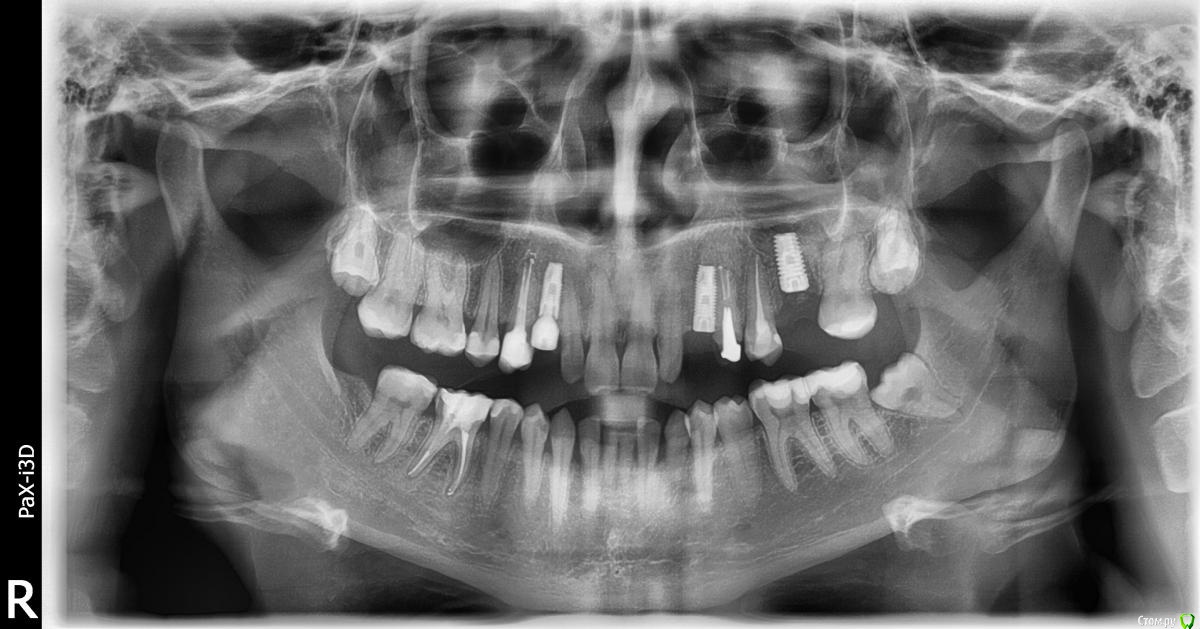

fifa888.dexo Опубликовано 22 июля, 2015 Автор Поделиться Опубликовано 22 июля, 2015 (изменено) Вот панорамный Изменено 22 июля, 2015 пользователем fifa888.dexo Ссылка на комментарий

diesel87 Опубликовано 22 июля, 2015 Поделиться Опубликовано 22 июля, 2015 По ОПТГ, формирователь не докручен, вам уже сказали, имплант в области левого клыка скорее всего не в контакте с четверкой (но надо глянуть КТ), даже если четверка депульпирована, она бы четко отреагировала бы на контакт с имплантом, болью или дискомфортом при накусывании/надавливании. В области синуса воспаление не особо просматривается и материал тоже четко не визуализируется в пазухе. Капать надо сосудосуживающее или гормональное. Выложите еще раз ссылку на КТ, ваши срезы не информативны. Ссылка на комментарий

diesel87 Опубликовано 22 июля, 2015 Поделиться Опубликовано 22 июля, 2015 http://fs2.directupload.net/images/150723/9sv48h7l.jpg http://fs1.directupload.net/images/150723/9nsd29hm.jpg http://fs2.directupload.net/images/150723/q4s456ou.jpg http://fs2.directupload.net/images/150723/9x7h27mc.jpg По КТ:1.возможно имплант в области клыка в апексе (самой верхней части) контактирует с четверкой (не ясно из-за того что имплант фонит), если четверка не реагирует, то пока наблюдать, делать прицельные снимки раз в 3/6/9/12 месяцев.2. Не докрученный формирователь, особо не страшно, но в щель может врасти десна, будет запах, локальное воспаление в области шейки импланта, так что лучше его докрутить или если он упирается в соседние зубы, поменять на узкий и докрутить.3. Имплант что в синусе, по снимку он практически весь в кости, а "воспаление" могло быть там и ранее, есть снимки до операции?? Ссылка на комментарий